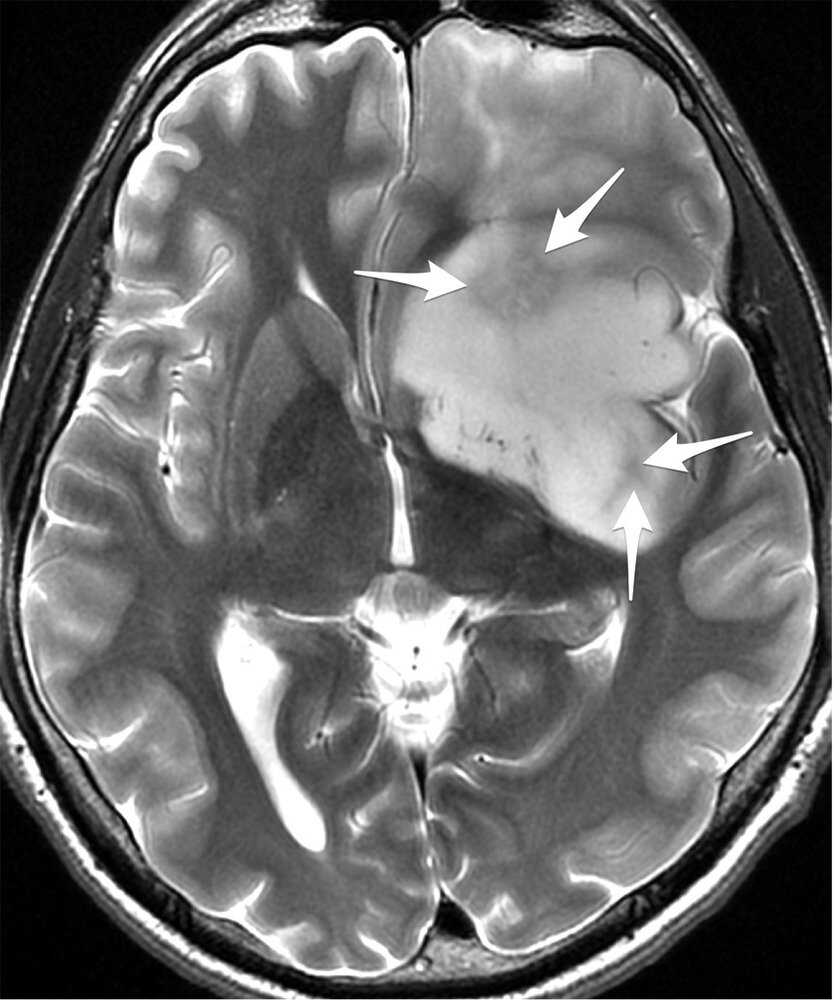

Глиомы, опухоли головного мозга, достаточно “капризны” в этом плане. Для комфортного существования им нужна внеклеточная жидкость, богатая питательными веществами, глюкозой и протеогликанами. Эти вещества создают “гелеобразню” среду, в которой нашим нервным клеткам жить и работать весьма комфортно.

Глиома. https://www.mediasphera.ru/system/photos/files/000/036/956/original/voprosy_neirokhirurgii_2015_06_01_ris2.jpg?1464701419